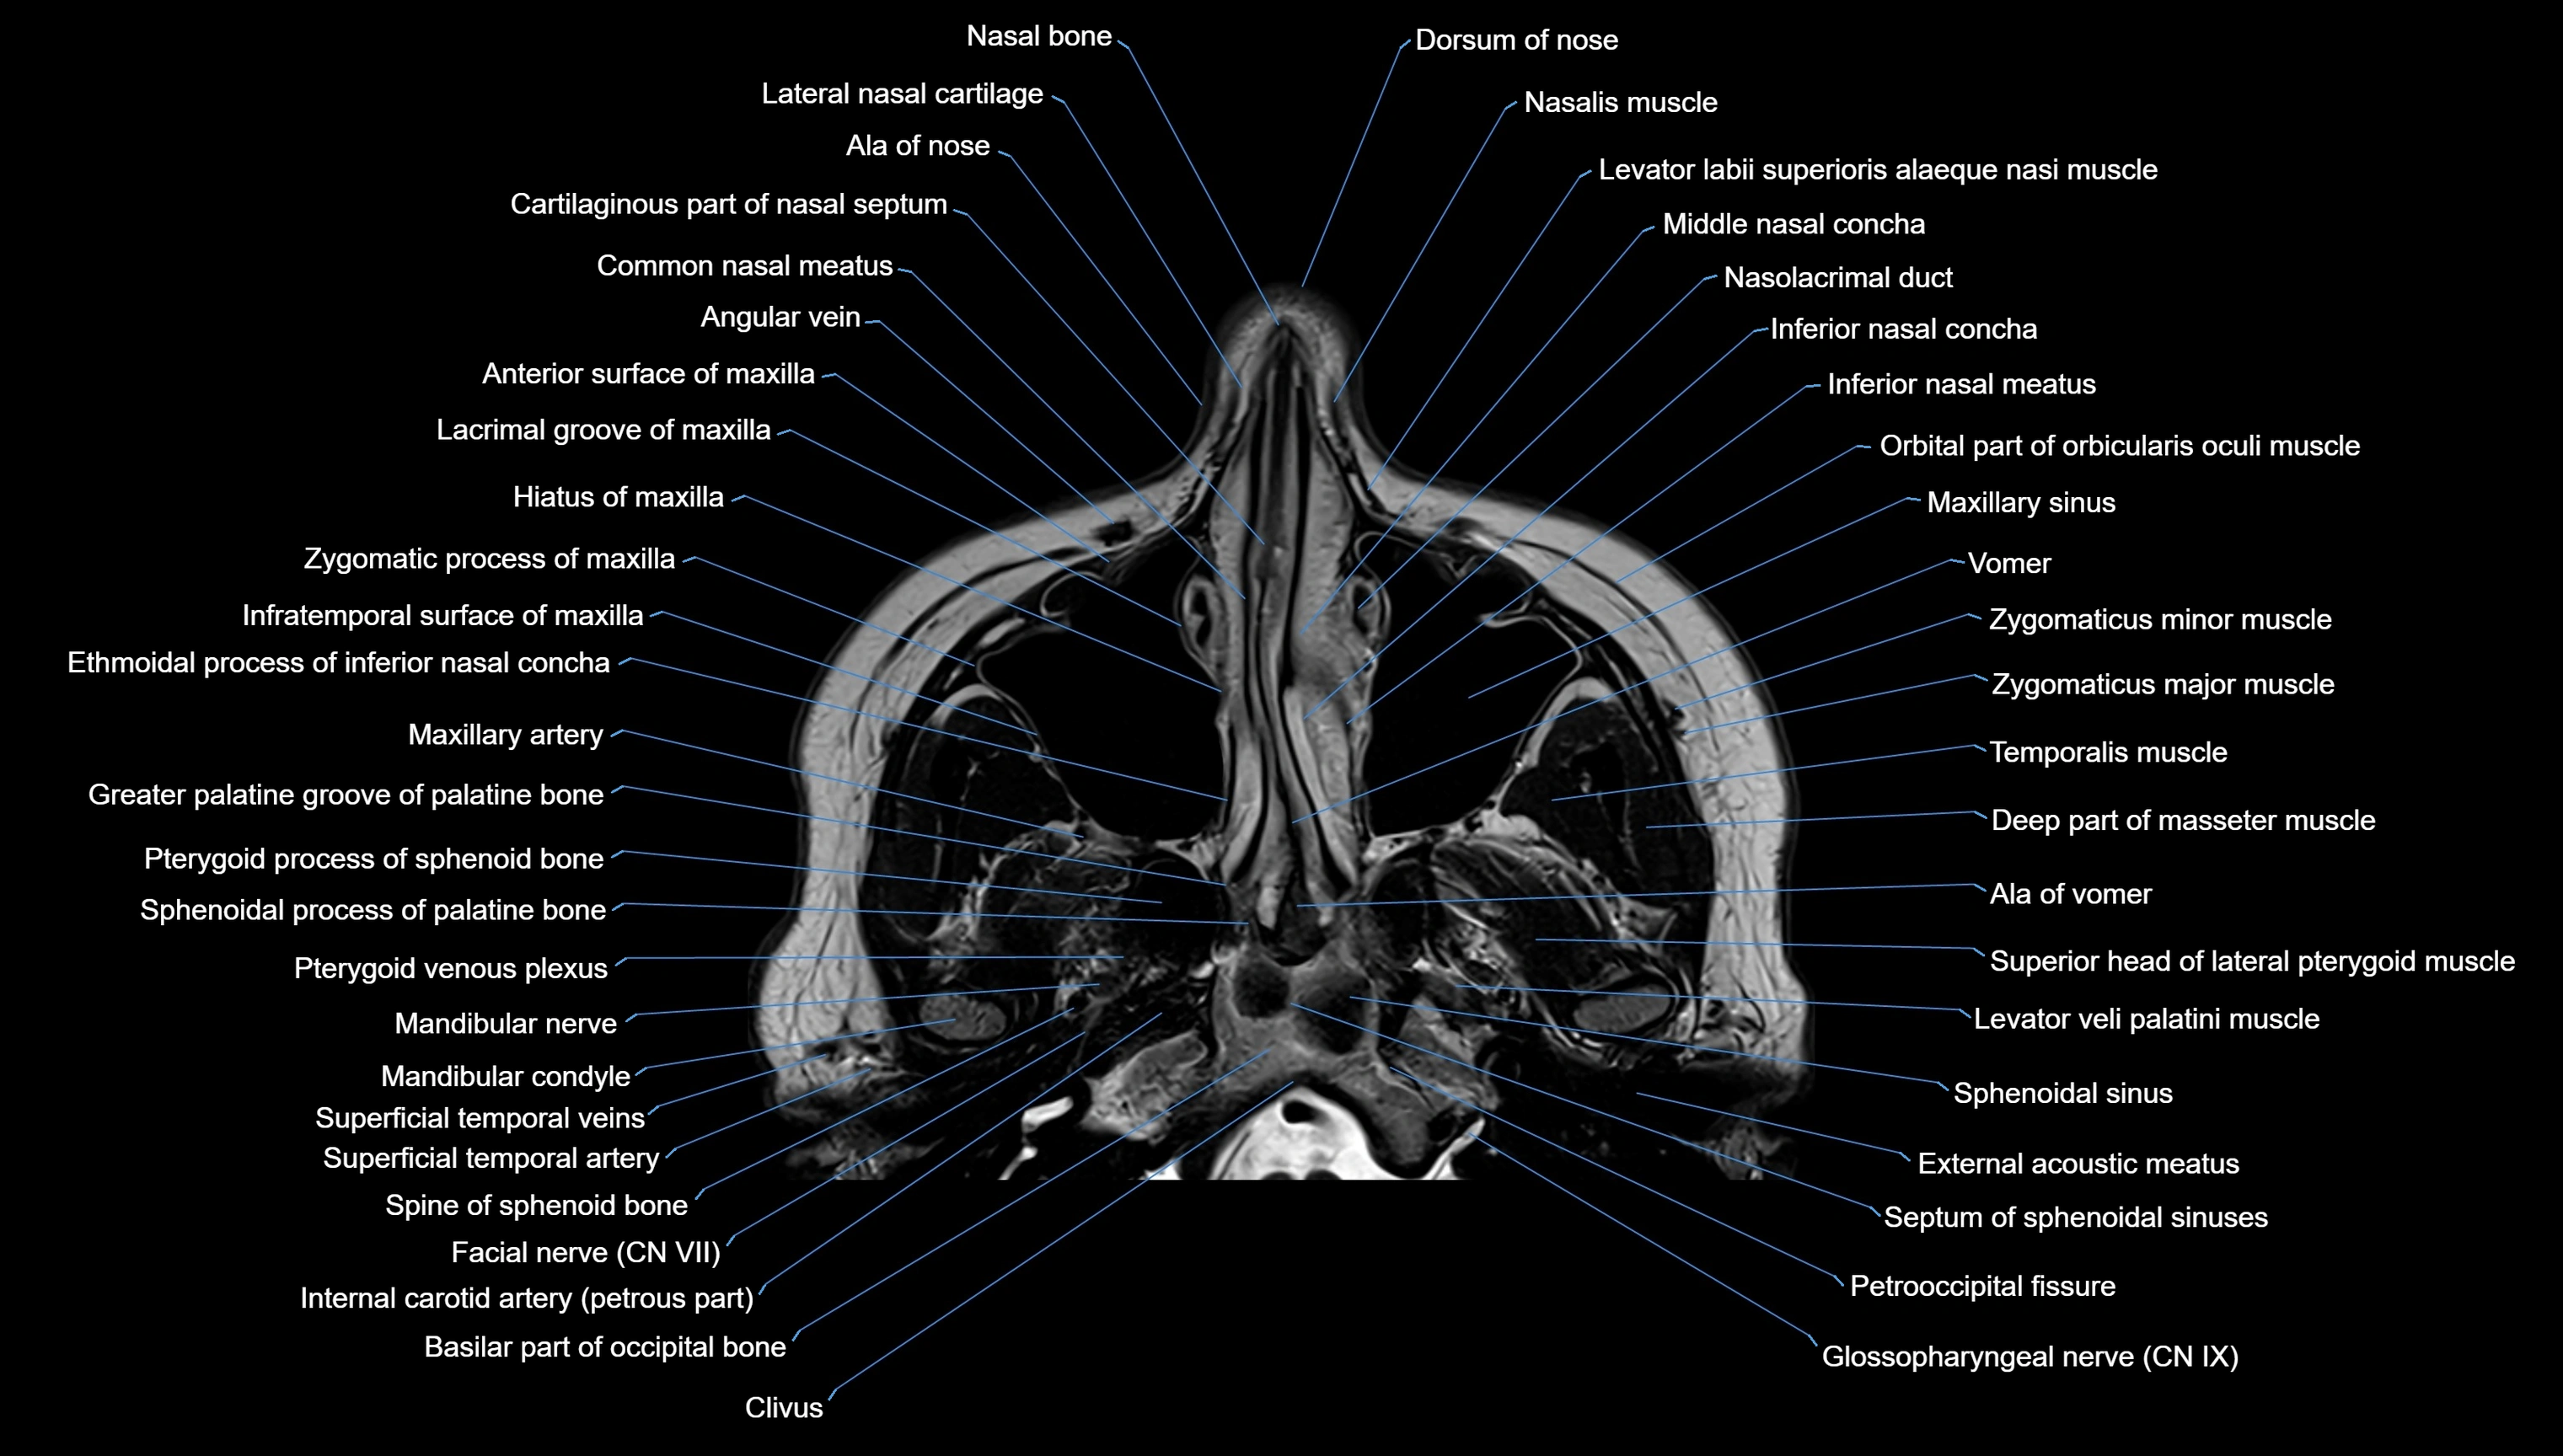

MRI images